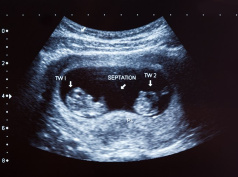

Роды двойни, как правило, отличаются от появления на свет одного малыша. Выше вероятность осложнений, должна быть постоянная готовность к оперативному родоразрешению. Одной из особенностей при вынашивании двух плодов часто являются преждевременные роды. Именно поэтому женщина, ожидающая нескольких малышей, более тщательно наблюдается специалистами на протяжении всей беременности.

По результатам ультразвукового исследования решается вопрос, какой способ родоразрешения будет оптимальным для данной беременной. Если последнее УЗИ показало, что наблюдается поперечное или диагональное расположение плодов, женщине будет предложена плановая операция.